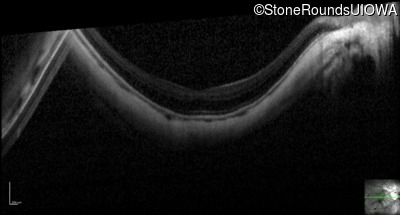

Optical Coherence Tomography - Left - 20/30 -2

Exemplar / OCT Stack

OCT Stack